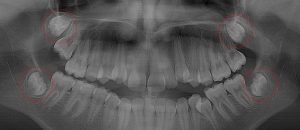

This 8 year old patient has 4 permanent 1st “6 year” molars fully erupted (circled). All 4 permanent 2nd molars are deep in the jaw on both arches and are just starting root formation (circled). There are no 3rd molar tooth buds evident below, but natural 3rd molar agenesis that occurs 7% of the time cannot be confirmed until age 14.